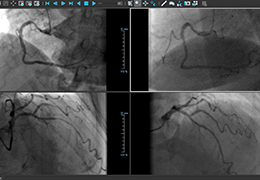

View X-Ray CT & MRI Scans Fast and Easily

Designed for surgeons, Pro Surgical 3D makes it easy to view patient scans quickly. Pro Surgical 3D facilitates the optimal 3D treatment and assessment workflows based on X-ray CT and MRI scans – and best of all, it’s FREE!

Designed mainly for CT and MR DICOM modalities.